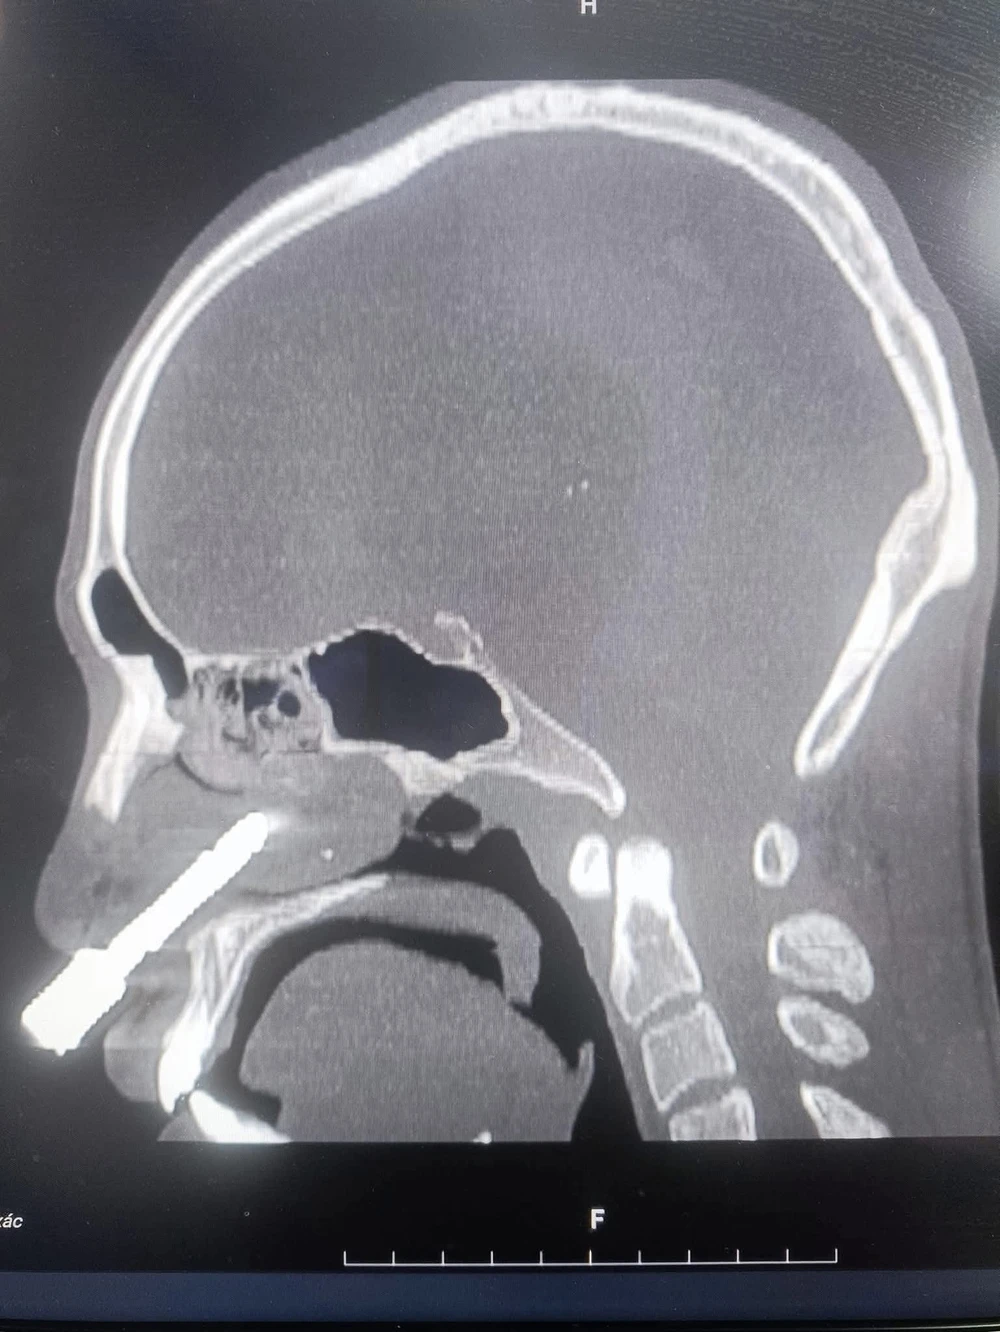

Kết quả chụp cắt lớp vi tính (CT-Scan) và dựng hình ảnh 3D cho thấy dị vật là một mũi khoan đá kim loại dài khoảng 7–8cm, có hình cong như lưỡi câu, đâm từ hốc mũi phải xuyên thủng vách ngăn mũi.

Hình ảnh mũi khoan đá cắm sâu trong lỗ mũi nam bệnh nhân.